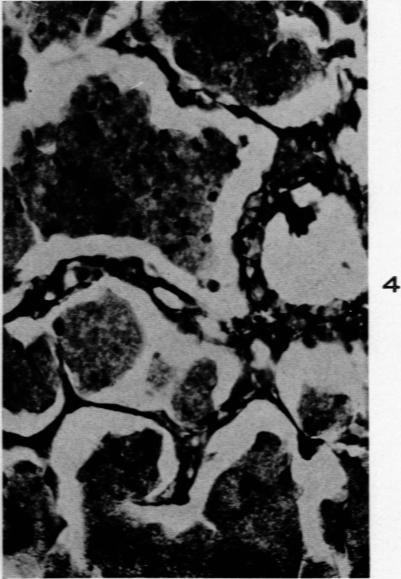

SCHEPERS G W

Am J Pathol. 1959 Nov-Dec;35(6):1169-87.